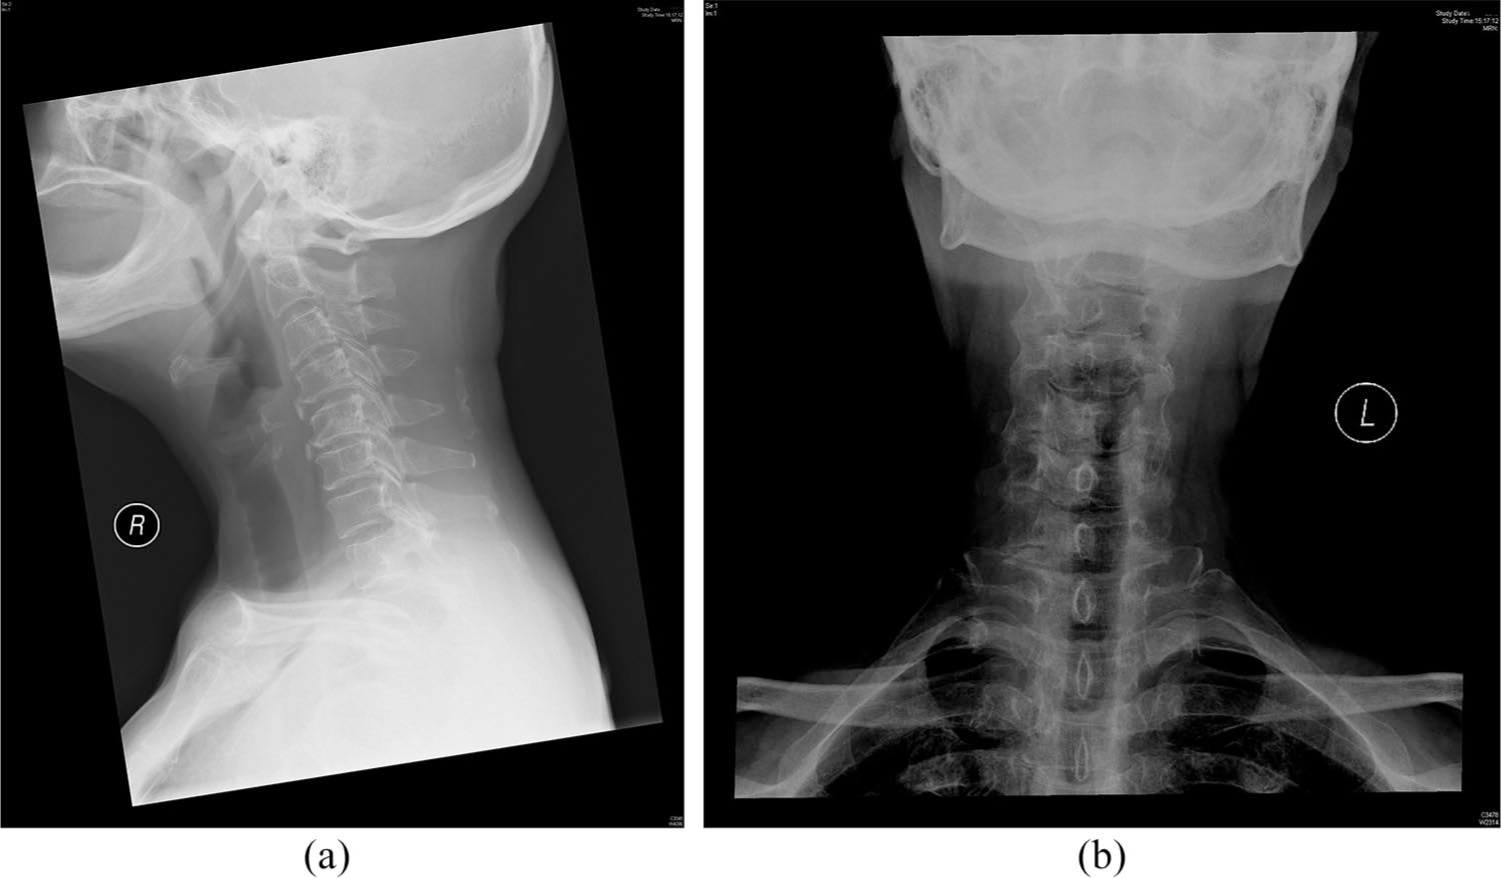

A lady in her 70s who is a smoker with hyperlipidaemia and suboptimal diabetic control complained of increasing neck pain for 5 months. The pain was insidious in onset, sharp in character and persistent in nature. It was worse when she moved her neck. There were no radiation, history of trauma, fever, limb numbness or weakness. She visited numerous doctors including a specialist in orthopaedics. Despite tramadol and physiotherapy, her neck pain showed no improvement. Other than the obvious distress, physical examination showed a stiff neck and bilateral paraspinal muscle tenderness. There were no spinal tenderness and cervical myelopathic hand signs. Upper and lower limbs examination revealed full strength, normal tones, normal deep tendon reflexes, and intact fine touch and pinprick sensation symmetrically. Range of movement of neck was full. A X-ray of her cervical spine was taken (Figure 1).

X-ray of her cervical spine: (a) lateral view and (b) anteroposterior view.

There is an elongated ossified stylohyoid ligament on the right, which measures 8.8 cm and angulates anteromedially.